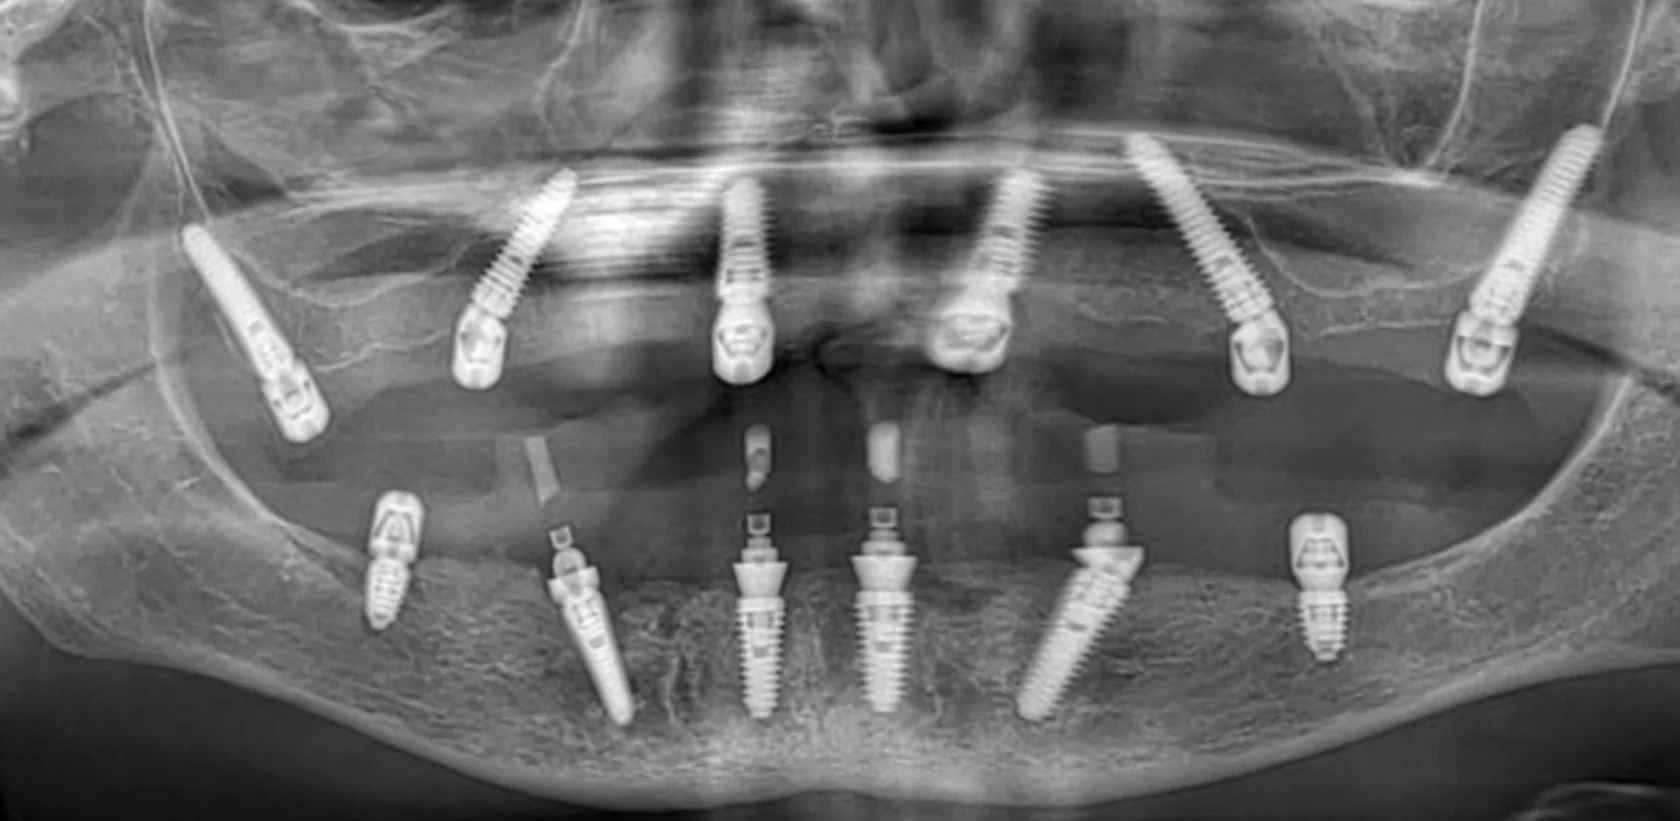

«Говорили, что это невозможно». Пациентка долго слышала, что в её ситуации полноценное восстановление зубов невозможно или потребует множества этапов и длительного лечения. Это останавливало её от решения проблемы на протяжении многих лет. Частичное отсутствие зубов на верхней и нижней челюсти требовало функционального и предсказуемого решения.

На консультации мы провели подробную диагностику и нашли варианты лечения. В итоге была выполнена тотальная реабилитация. В день операции установлены имплантаты и несъёмные конструкции.

Уже через 4 часа была восстановлена жевательная функция и anti-age-эффект за счёт правильной опоры мягких тканей.

Долгое время пациентка стеснялась улыбаться и избегала фотографий из-за проблем с зубами и неудобных съёмных конструкций. Она откладывала лечение, считая, что восстановление будет долгим и тяжёлым. Отсутствие зубов на верхней и нижней челюсти требовало надёжного и долгосрочного решения.

На консультации мы подробно обсудили все варианты и выбрали современное и комфортное решение. Было выполнено полное восстановление зубных рядов по концепции All-on-6 с немедленной нагрузкой. В день операции установлены имплантаты и несъёмные протезы.

Сегодня пациентка улыбается уверенно, свободно общается и возвращается к привычной активной жизни без прежних ограничений.

Пациент долго откладывал лечение, сомневаясь в необходимости серьёзного вмешательства и опасаясь сложной операции. Но со временем неудобства и ограничения в повседневной жизни, особенно во время приёма пищи, стали перевешивать сомнения.

На консультации мы подробно разобрали все этапы лечения, обсудили возможные риски и подобрали понятный и комфортный план. В итоге была проведена реабилитация верхней и нижней челюсти по концепции All-on-6 с немедленной нагрузкой. В день операции установлены имплантаты и несъёмные конструкции.

Сегодня пациент признаётся, что зря так долго сомневался — результат превзошёл его ожидания.

Долгие годы жил без полноценного зубного ряда из-за страха большой операции. На консультации всё очень подробно рассказали и убедили, что процесс будет комфортным и не вызовет неприятных эмоций.

Провели реабилитацию верхней и нижней челюсти по концепции All-on-4 с немедленной нагрузкой. В день операции установлены имплантаты и несъёмные протезы.

Теперь точно все страхи позади. Пациент улыбается уверенно и ест без ограничений.

Долгое время откладывал лечение, потому что боялся сложной операции и долгого восстановления. Жил с постоянным дискомфортом и ограничениями в питании, но не решался сделать первый шаг. Длительное отсутствие зубов на верхней и нижней челюсти привело к потере жевательной эффективности и опоры мягких тканей.

На консультации мы подробно разобрали все этапы лечения, ответили на все вопросы и подобрали комфортный и безопасный план. По протоколу All-on-4 на обеих челюстях установлены несъёмные конструкции.

Уже в день операции пациент получил новую улыбку. Обеспечена стабильность прикуса, полноценная функция и выраженное улучшение лицевых пропорций за счёт восстановления опоры тканей.